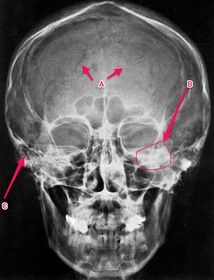

Anatomy practical midyear flashcard revision

anatomy

x-ray